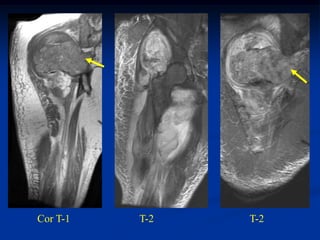

Case #1170.1              P.O. desmoid

61 year female with OA knee in 3/06 prior to TKA

Sag MRI 4/03

T-1                  T-2

MRI 1 year PO TKA

Sag T-2                       Gad

Axial

Gad

Surgical resection